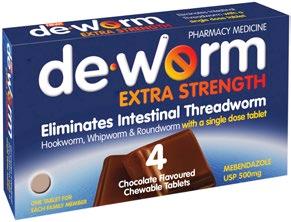

Eliminates intestinal threadworm with one single-dose tablet Chocolate flavoured chewable tablets Available in packs of 2, 4, 6 and new 10 Tablet Family Pack Soothes the throat Contains Manuka honey Supports immune heath Blended with Wellmune® for immune health support and natural New Zealand Manuka honey to coat the throat. Bursting with delicious and soothing flavours. Effective worm treatment Soothe dry, tickly throats De-Worm Extra Strength 500mg 2 Tabs $699 4 Tabs $999 6 Tabs $1199 $1399 Multichem NZ Ltd, Auckland $699 20 Tabs Radiant Health Ltd, Auckland Pharmac y only me dicine O ne t ablet once for any memb er of the family 2 year s and over Radiant H ealth Ltd , Auckland SEE F ULL RANGE I N S T O R E GREAT CHOCOLATE FLAVOUR KI LL S WO RM S ONE TABLET ONCE Vermox Choc Chews 4 pack $1399 De-Worm Extra Strength 500mg Family Pack 10 Tabs Offers and advertised products may not be available at all participating pharmacies. Offers are valid from Monday 6 March to Friday 24 March 2023 or while stocks last. Prices printed in this brochure are Recommended Retail Prices (RRP). Always read the label. Use only as directed. If symptoms persist see your doctor or health professional. Vitamins are supplementary to a balanced diet. Full product information is available from your pharmacy TAPS PP9728. BACK TO SCHOOL ESSENTIALS